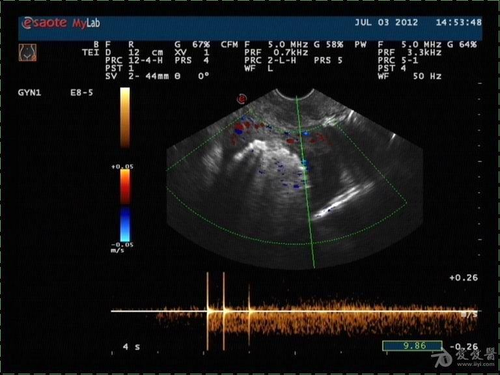

一般女性去做全身检查,最好对自己子宫进行一番检查为好。检查结果出来,若自己身体没任何问题自然是好,可是有些人被告知自己子宫内有杂乱声音,便十分担心。那么,女性子宫腔内杂乱回声是什么回事呢?

女性子宫内杂乱回声的原因可能是自己子宫内膜发炎,一般可能是月经不调或者流产后调理不好等导致;或者是子宫内膜有残留异物或者积血,使得子宫内膜发生病变,因此能够听到女性子宫内有杂乱回声。